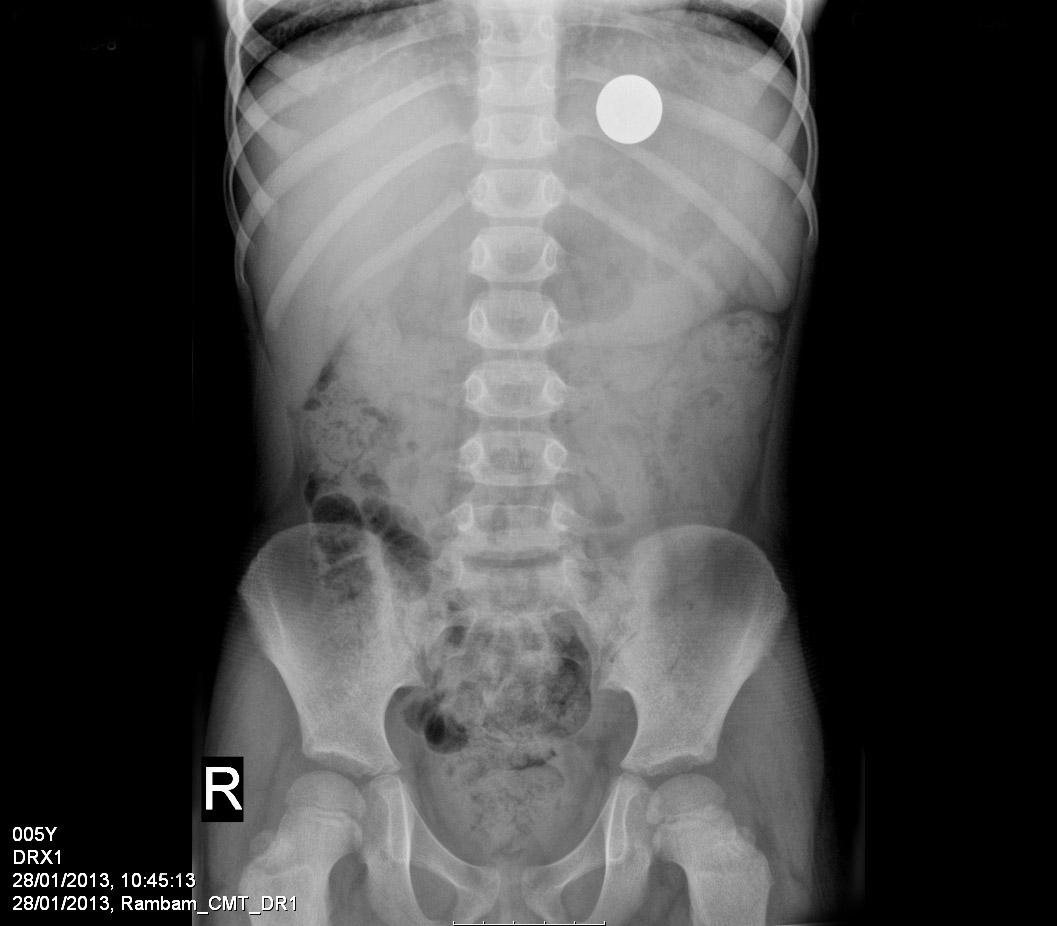

בתמונה: צילום הרנטגן של י', לפני הוצאת המטבע. קרדיט צילום: דוברות רמב"ם.

י', בן חמש מאזור חיפה, ניסה לבצע "ניסוי מדעי" בביתו, אך במילותיו של הפעוט עצמו "הניסוי כשל". הפעוט הסקרן הכניס לפיו מטבע של עשר אגורות, והצמיד ללחיו מגנט. מטרת הניסוי הייתה לבדוק, האם הוא יוכל להזיז את המטבע שבפיו, בעזרת המגנט שהוצמד ללחי, אולם במהלך הפעולה, למדען הצעיר אירעה "תאונת מעבדה" והוא בלע את המטבע.

כאשר ההורים הבינו באיזה ניסוי מדובר, הם מיהרו להגיע לאחת ממרפאות קופ"ח שבאזור מגוריהם, אולם שם ייעצו להם להמתין עד שהטבע יעשה את שלו. במשך שבועיים ימים המתינו הוריו של בן ה-5 ליציאתו של המטבע מגופו בדרך טבעית, כאשר הם עוקבים באמצעות סריקות אחר תנועת המטבע בקיבתו של הילד, אולם לבסוף, בעצת הרופא המטפל בקהילה, הוחלט להביא את הפעוט אתמול לרמב"ם בכדי לסייע בהוצאת המטבע.